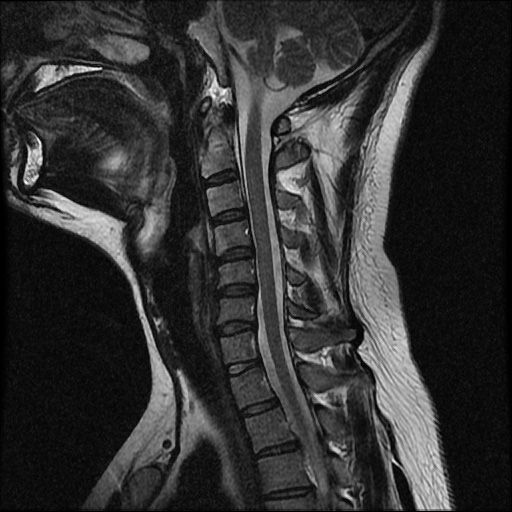

이 MRI 사진은 21년도 사고 당시 찍은 MRI 사진 입니다. 확인 부탁드립니다~

전체 mri를 다 봐여겠지만 보여주신 mri 컷에서는 의미있는 경추 디스크탈출이 보이지 않습니다.